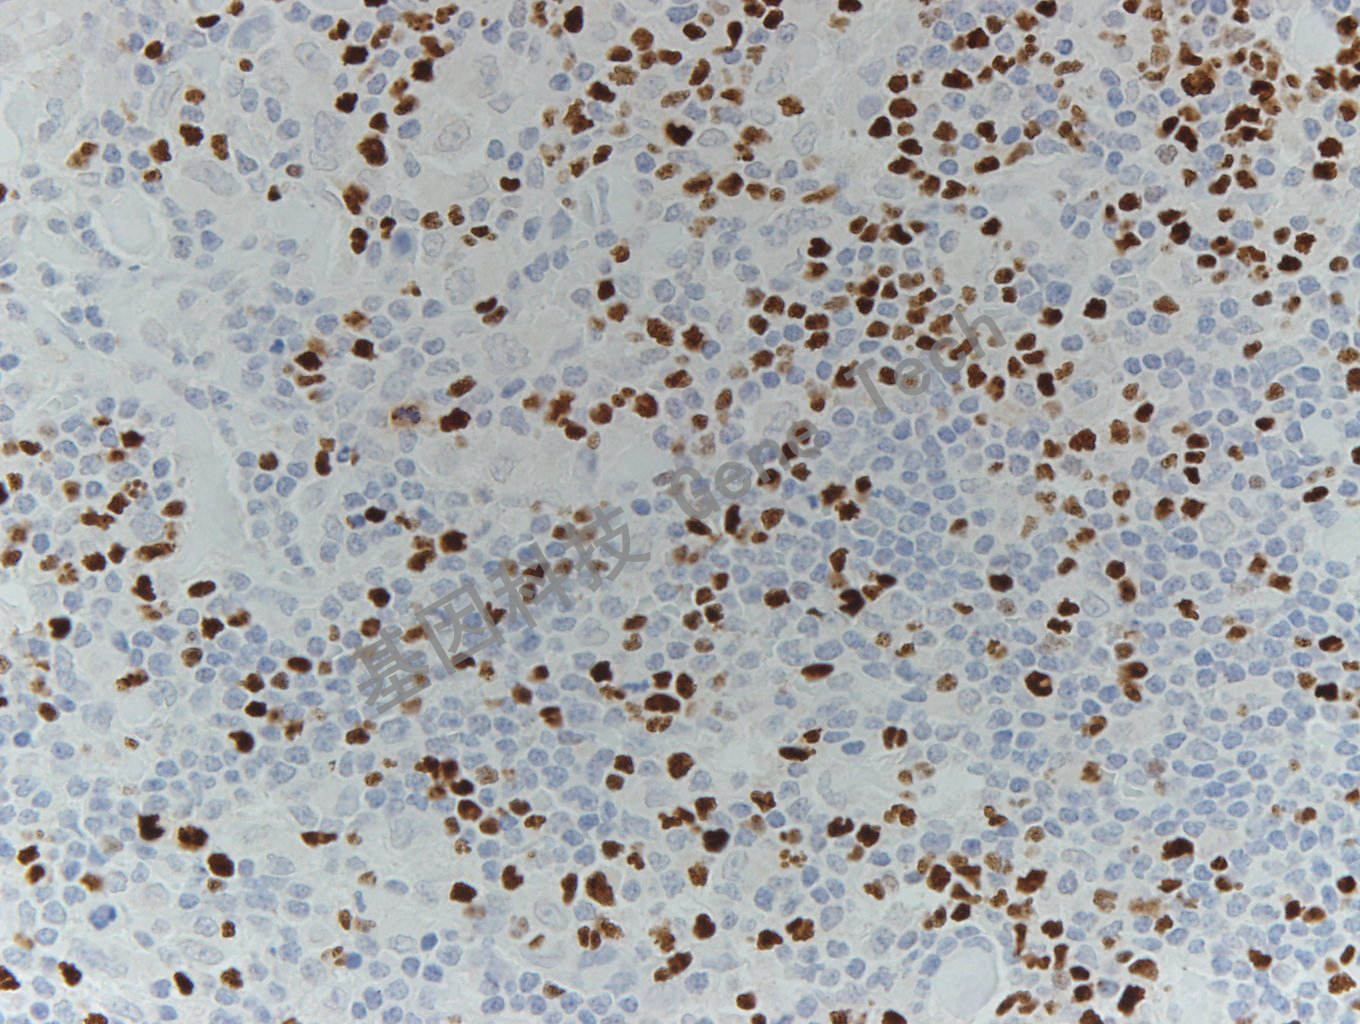

| 預(yù)處理:高pH熱修復(fù) | 陽性部位:細(xì)胞核 | 陽性對照:套細(xì)胞淋巴瘤 |

| 套細(xì)胞淋巴瘤石蠟切片,用 FoxP1(GT2184)染色,細(xì)胞核陽性,DAB 顯色。 | ||